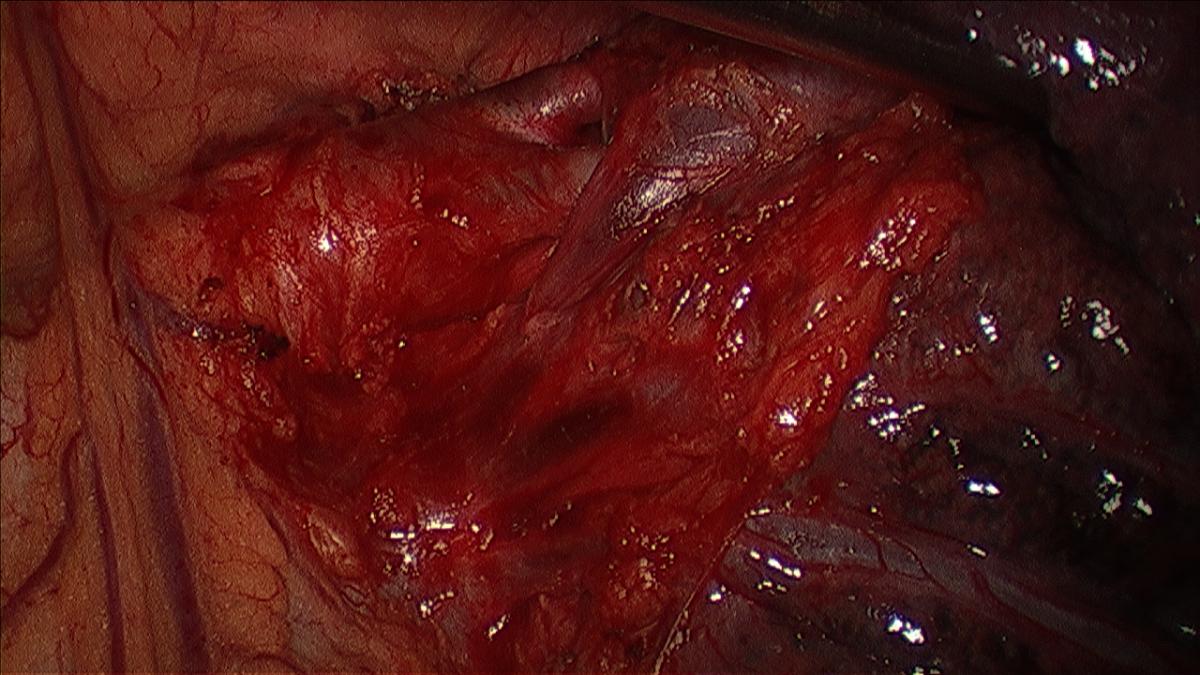

The first pulmonary arterial branch to the left upper lobe, which is the artery to the apico-posterior segment, is dissected sharply and bluntly if adequate exposure is possible. The exposure of the artery is facilitated by retracting the superior vein inferiorly with the sucker (Figure 4, 5).

Any lymph nodes encountered are dissected, removed, and analyzed as described. If exposure is not adequate, the apical tri-segmental vein can be divided as described subsequently. Circumferential isolation of the artery is performed with a thoracoscopic right angle, or curved vascular clamp via the working incision (Videos 3, 4).